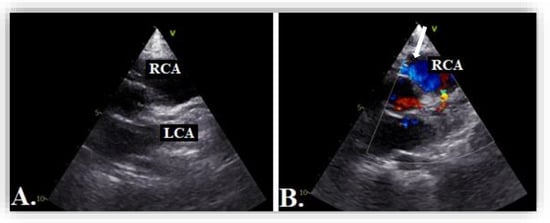

3. Case Report #2